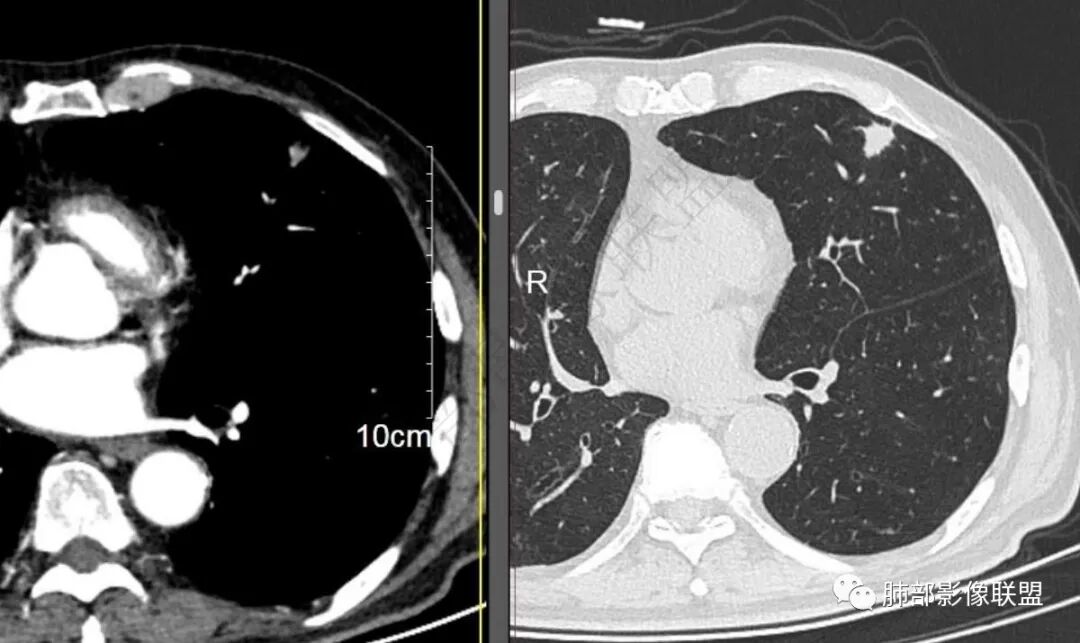

二..发现左肺上叶舌段实性密度小结节影,不规则略呈半环形,边界清楚,未见分叶、毛刺及磨玻璃晕。未见卫星病灶。

9个月后病灶明显增大,边缘较平直,部分膨隆,锁扣样外观,仍旧缺乏典型深分叶及张力,未见胸膜凹陷。

再1个多月后病灶继续增大,较明显不均匀强化,肺门一侧见低密度区。病灶边缘相对不清,可见毛刺。